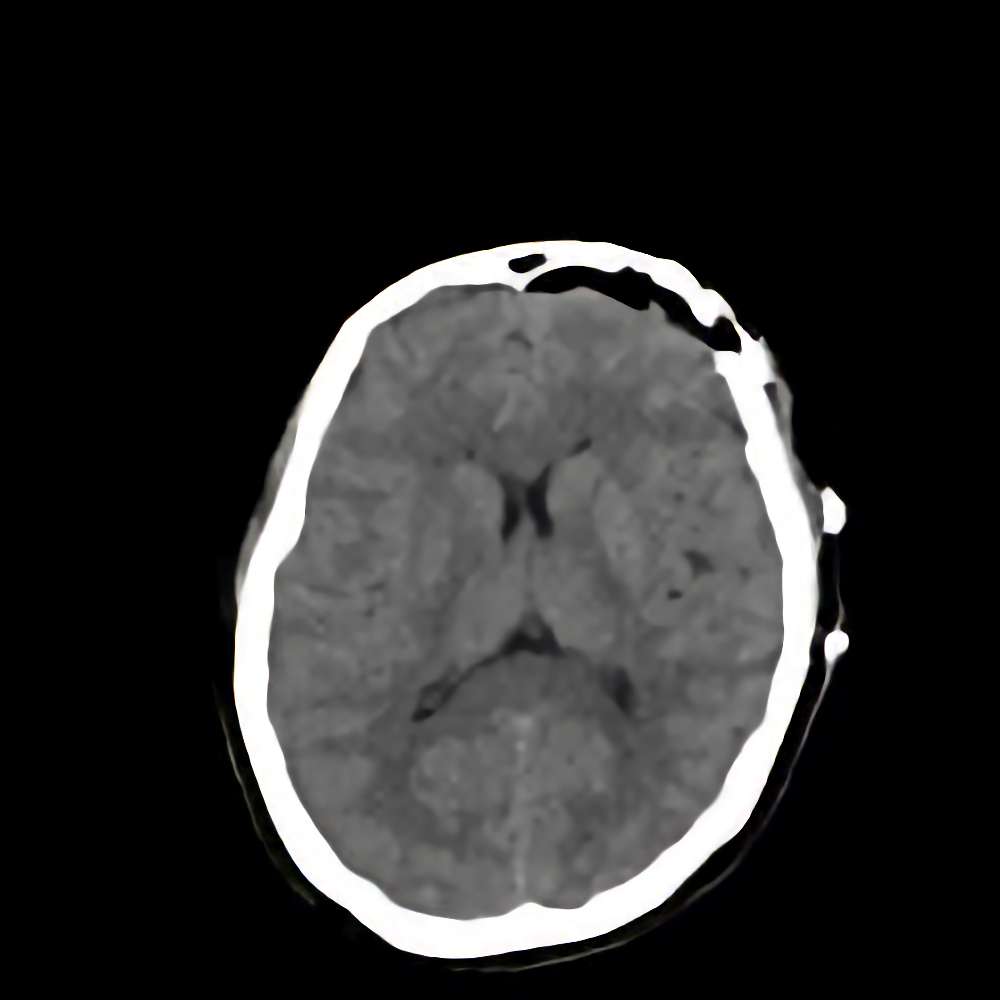

症例 '16年5月

No.

※ 画像をクリックすると拡大表示します。症例No.は平成29年から起算しています。

年_番号

手術年月

患者年齢

’16_68

'16年5月

40代

病名

術式

備考

髄膜腫

断層撮影

手術前

1

手術前2

手術後